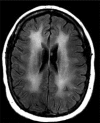

Illicit drug use can result in a wide range of medical complications. As the availability, synthesis, and popularity of illicit drugs evolve over time, new syndromes associated with their use may mimic infections. Some of these symptoms are anticipated drug effects, and others are complications of adulterants mixed with drugs or complications from the method of using drugs. Some illicit drugs are associated with rare infections, which are difficult to diagnosis with standard microbiological techniques. The goal of this review is to orient a wide range of clinicians-including general practitioners, emergency medicine providers, and infectious diseases specialists-to complications of illicit drug use that may be underrecognized. Improving awareness of infectious and noninfectious complications of illicit drug can expedite diagnosis and medical treatment of persons who use drugs and facilitate targeted harm reduction counseling to prevent future complications.